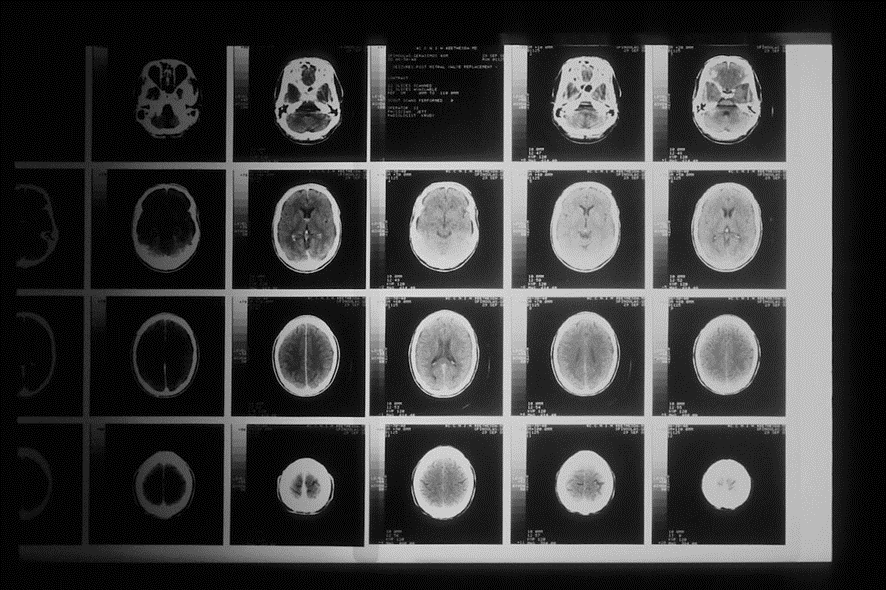

En la actualidad, comenta Alex Fornito, «la IRM (imagen por resonancia magnética) permite registrar cambios de actividad que se producen en segundos y en regiones que abarcan unos pocos milímetros»; mientras que la electroencefalografía (EEG) y la magnetoencefalografía (MEG) son mucho más rápidas, pero tienen menos resolución. Hay bastantes startups asentadas sobres estos campos.

¿Por qué no podemos ver el cerebro en tiempo real sin mecanismos invasivos?

La respuesta corta es porque «cerebro es un sistema muy complejo» que, «en su nivel más fundamental, está formado por miles de millones de neuronas conectadas por billones de fibras«, explica Alex Fornito. A medida que estas se enlazan para formar redes, son capaces de soportar pensamientos. Pero nosotros no podemos verlos, aunque ha habido intentos.

Como señala Alex Fornito, «los escáneres cerebrales humanos son cada vez más potentes y mejoran constantemente su resolución espacial y temporal», por lo que no sería de extrañar que en cierto momento salieran del laboratorio o los hospitales, como pasó con los medidores de pulso, de tensión o los oxímetros. Aunque no estamos cerca de nada parecido.